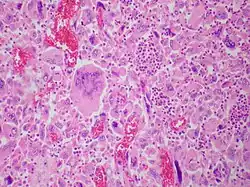

Pulmonary giant cell carcinoma represents a rare variety of non-small cell lung carcinoma that is characterized by the presence of numerous tumor giant cells and an influx of inflammatory cells that are mostly polymorphonuclear leukocytes admixed with macrophages. The dense oval aggregates of polymorphonuclear leukocytes seen in this image are probably located in the cytoplasm of tumor giant cells (emperiopolesis) that have been sectioned in a plane that does not include their nuclei.

Both "tumor cell-tumor cell" and "leukocyte-tumor cell" emperipolesis (i.e. active penetration of the latter by the former) is very commonly seen in cases of GCCL.[12]